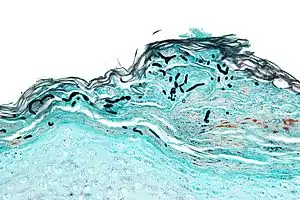

| Micrograph of a superficial dermatomycosis. The fungal organisms are the dark staining, thick, quasi-linear objects below with skin surface. Vulvar biopsy. GMS stain. | |

Examples of dermatomycoses are tinea and cutaneous candidiasis.These fungal infections impair superficial layers of the skin, hair and nails.